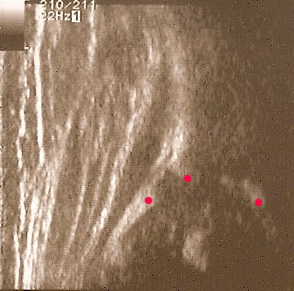

2.Otrzymanie następującego obrazu usg(rys.l):

- 1 sylwetka kości biodrowej z występem kostnym na końcu

- 2 wyraźny,umożliwiający identyfikację obrąbek stawowy

- 3 gałąź dolną kości biodrowej jako jasne,dobrze zaznaczone,silne echo

przekrojowy obraz usg w standardowej płaszczyźnie Brak któregokolwiek ze składników uniemożliwia prawidłową ocenę

i należy badanie powtórzyć.W taki sposób otrzymany obraz pozwala na wykreślenie kątów za pomocą następujących linii(rys.2):